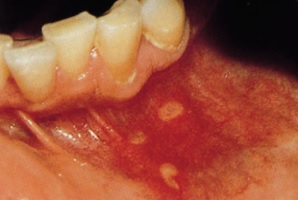

구내염의 가지 수에는 첫 번째로 궤양의 종류인 아프타성 궤양이 있어요. 뺨과 혀, 입술 안쪽에서 생기는 붉은 고리 속 옅은 노란색 궤양의 형태를 보입니다.

재발성 질병인 아프타성 궤양의 원인은 유전성, 많은 면역반응, 염증성 사이토카인의 증가와 관련이 있을 것으로 가설하고 있습니다.

구강 내 자극으로 인한 스크래치가 생겼거나 많은 스트레스와 피로를 최고 많은 사유로 짐작하였으있다고 합니다. 복취하는 식단(커피, 초콜릿, 치즈, 감귤류, 견과류, 감자..)이나 약물, 임신 중 그렇지 아니하면 피임약 복용 중에 발생하기도 하며 금연을 할 때에 나타나는 기회가 잦다고 하고요.

또 비타민B, 철분, 엽산이 부족할 때에도 일으켜서 난다고 합니다.